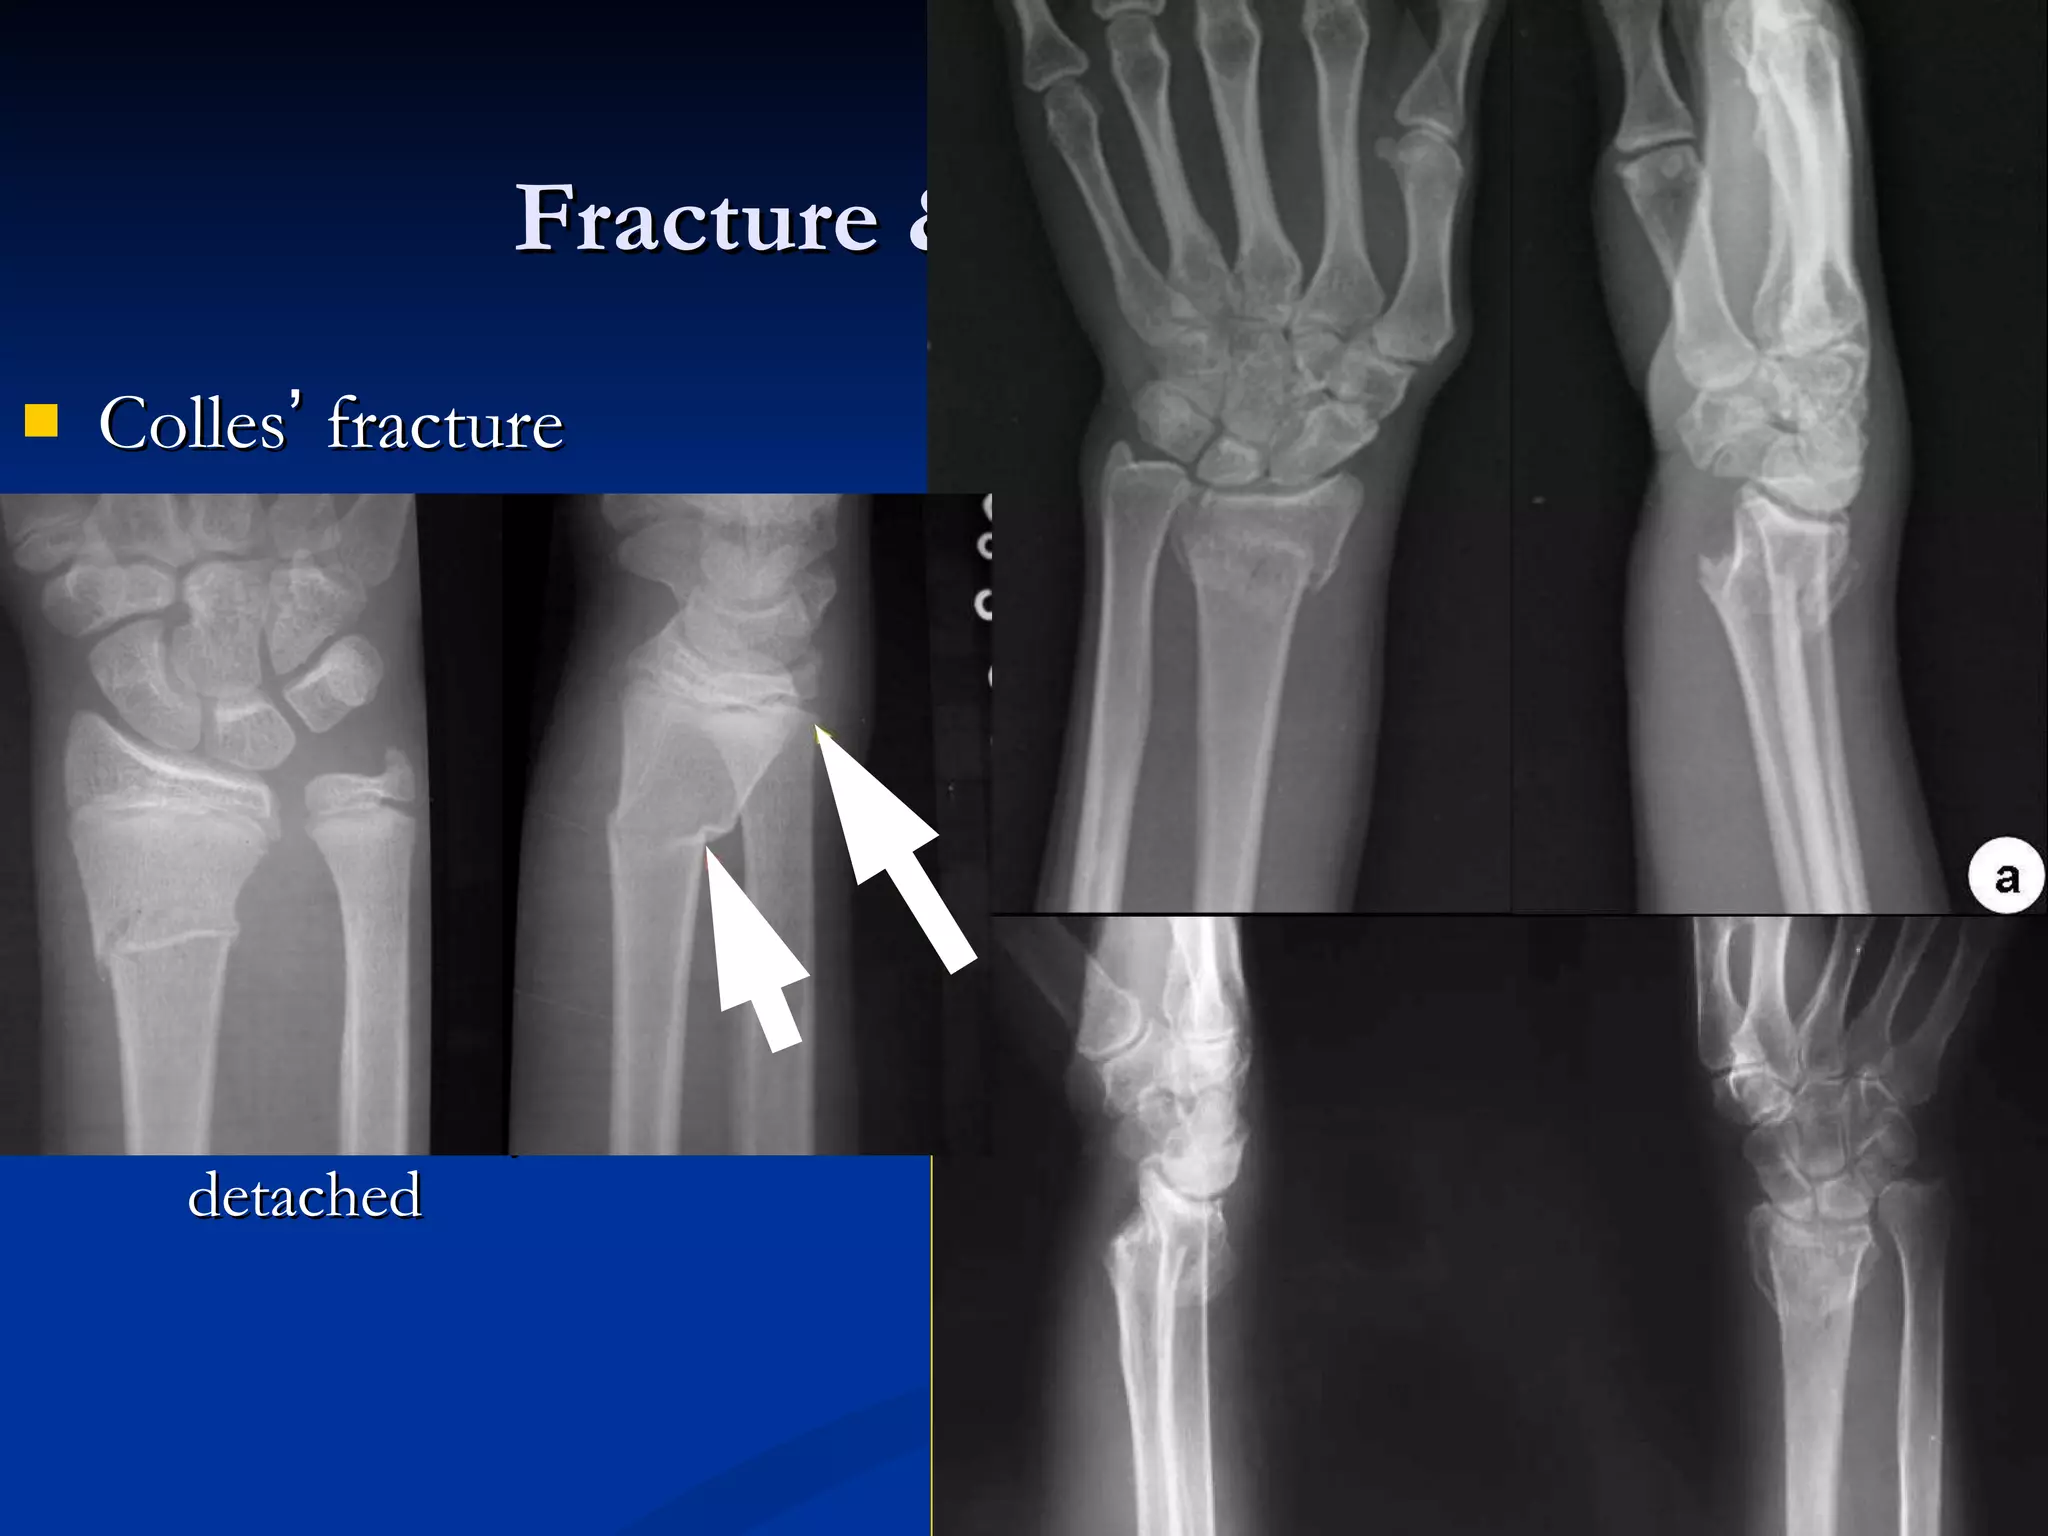

Normal X-ray appearances Joint  Synovial joint  -- knee  Fibrous joint --  Cartilaginous joint -- SI Synostosis joint  –  skull

Normal X-ray appearancesJoint Synovial joint -- knee Fibrous joint -- Cartilaginous joint -- SI Synostosis joint – skull